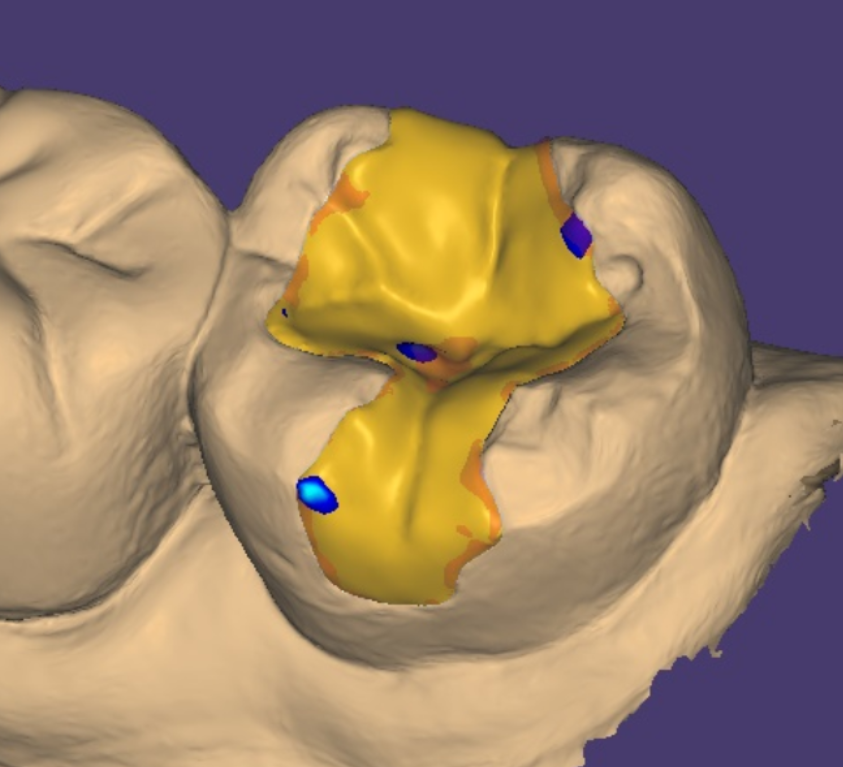

때문에 보철을 어떻게 만들지

제가 디자인 하고

찾아볼 수 있는것이 장점입니다!

상일동역 임플란트 전악 치료를 하시거나

교합이 일반적이지 않은 (반대로 무시거나)

치료가 어려운 케이스의 경우

돌려보면서 어떻게 제작할지

결정합니다.